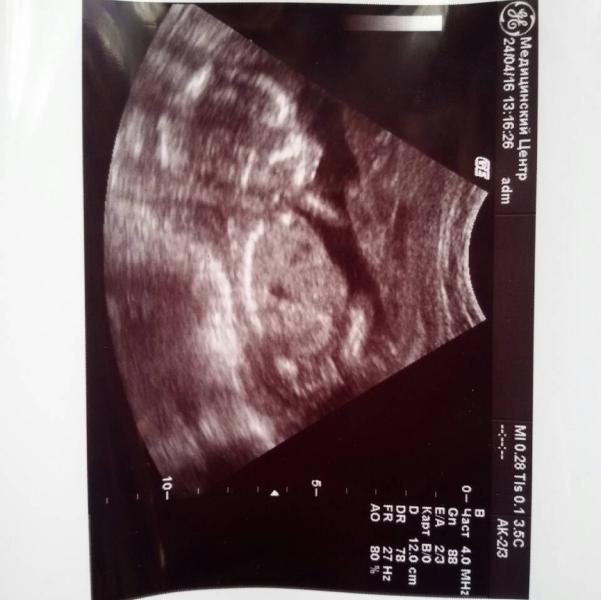

тут нам ровно 17 неделек, но узистка сказала , что по рост и вес как на 18-19 неделе

и еще узистка сказала, что краевое предлежание плаценты, у кого было?как рожали?и поднялась ли плацента?